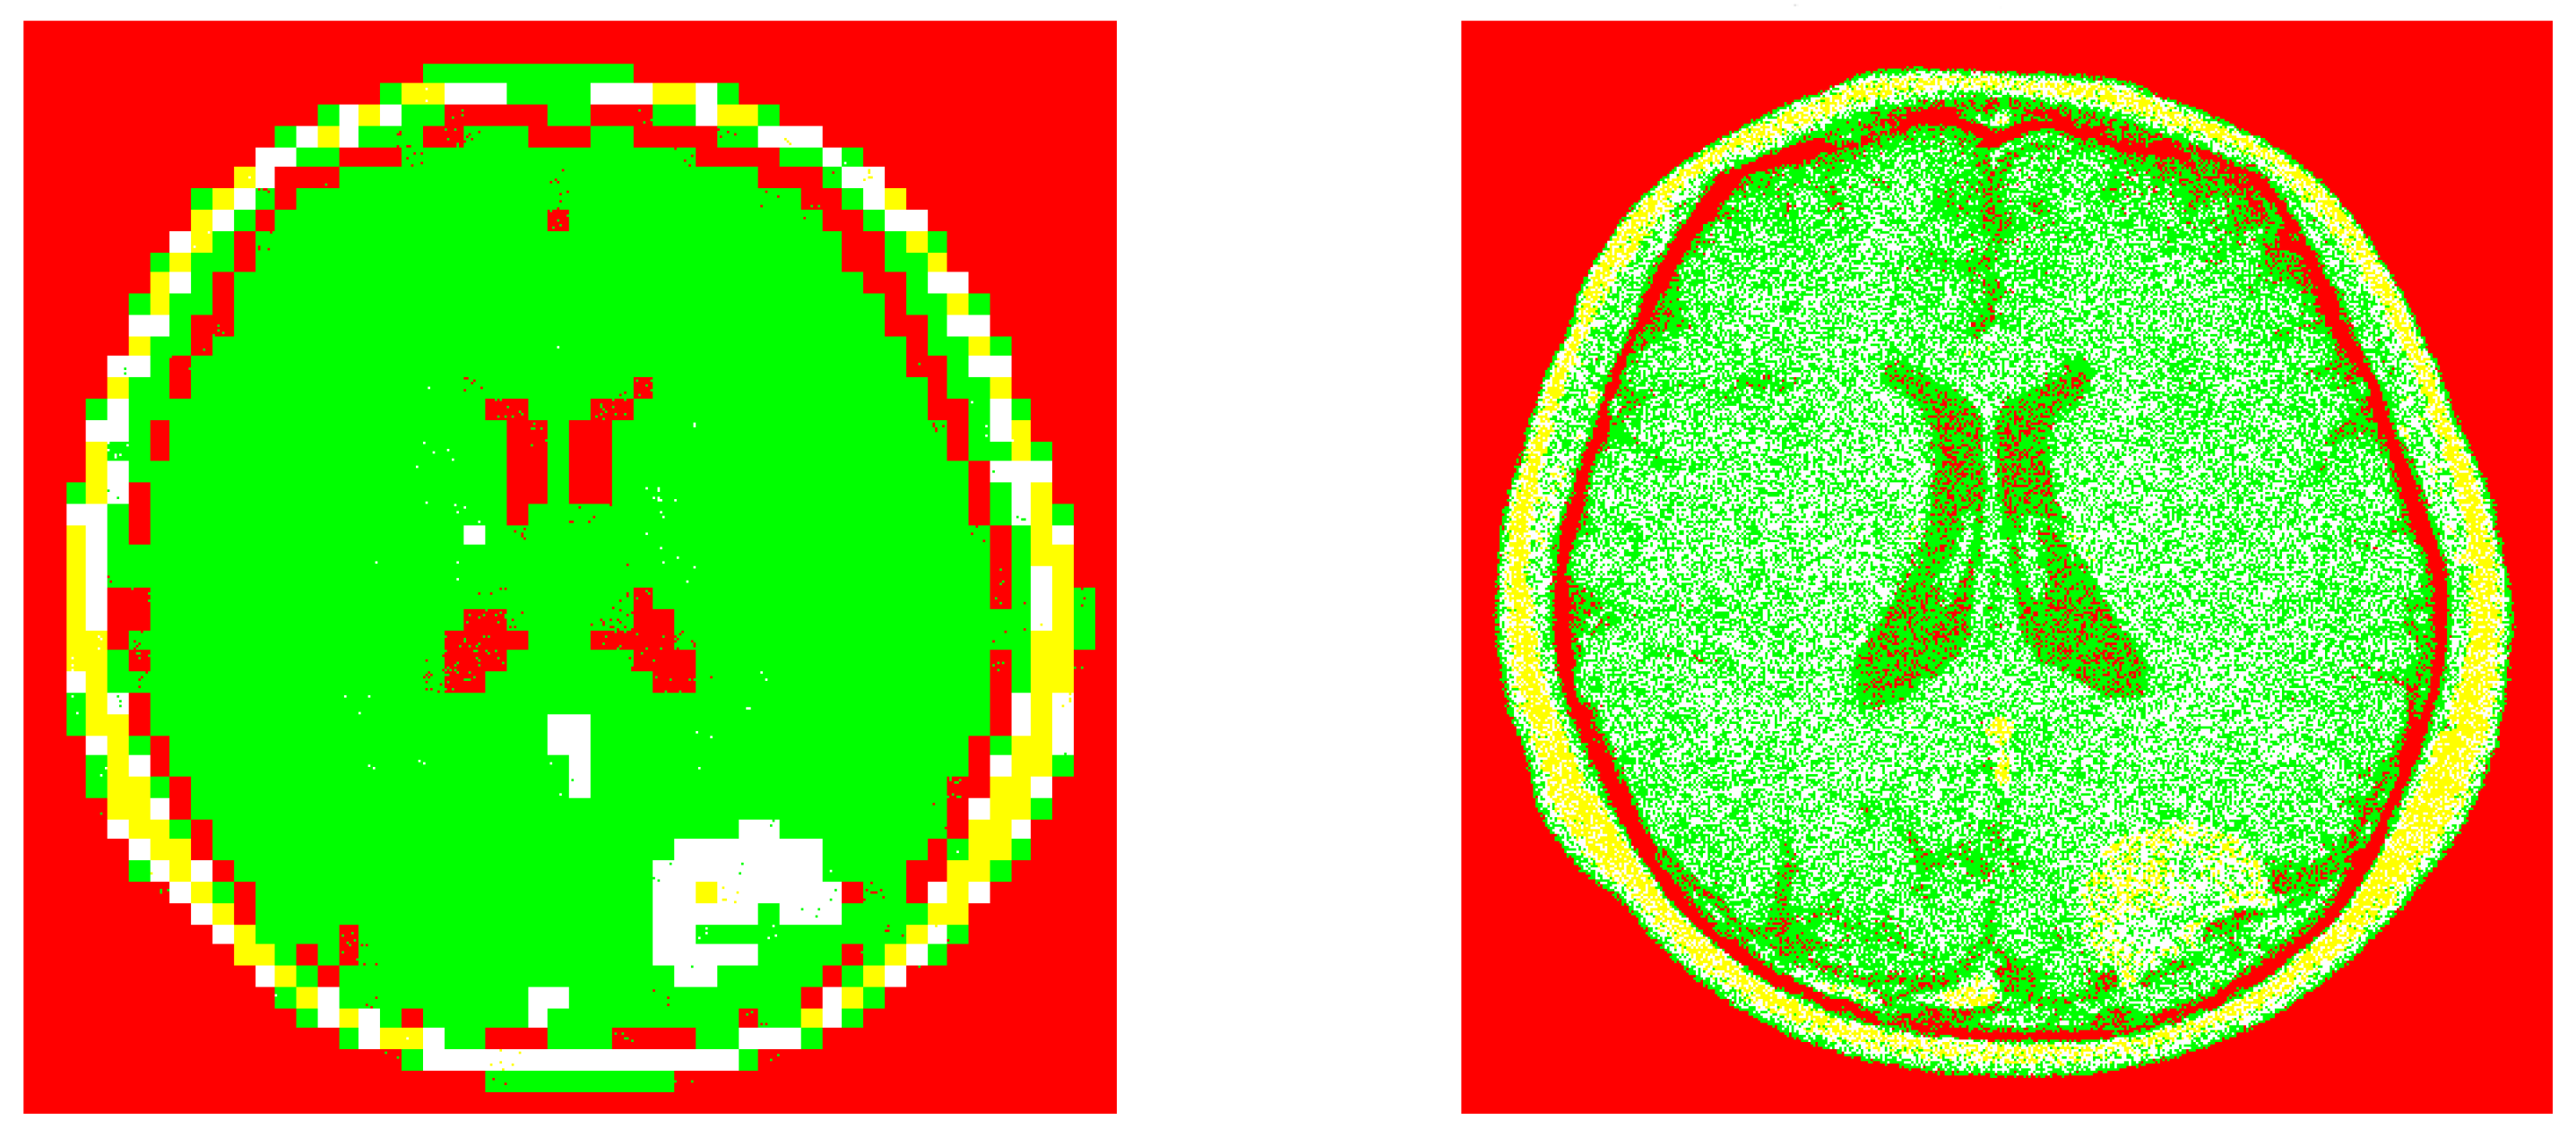

The corresponding image segmentations (from the example 1). Left: Processed image by using our design. Right: Processed image by invoking the reference method.

Figure 6.

The pre-processed image by using our IC method (from the example 1).

Figure 5.

The original speckle noisy image (example 1) with .

Figure 4.

This late expression was employed in our computation algorithm. Obviously, we have implicitly assumed that our sample dataset size is large enough to validate the Central Limit Theorem. Some numerical experiments are shown in Figure 4, Figure 5, Figure 6, Figure 7, Figure 8 and Figure 9. Next are some remarks.